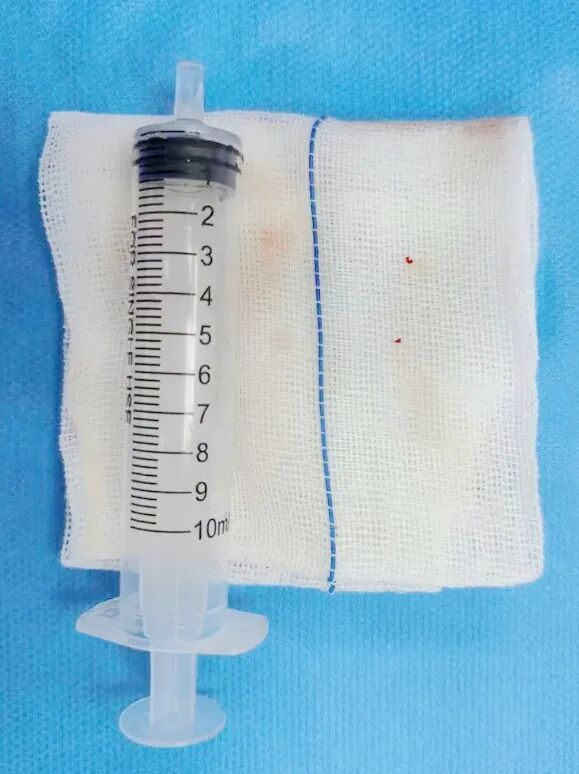

▲取出的血栓

在神经内科二区主任朱敏真指导下,张文胜主治医师、古鸿力主治医师紧急为患者实施了脑血管造影和血管内介入治疗术。术中发现左侧大脑后动脉P1段显影模糊,考虑局部存在血栓,同时Percheron动脉显影不清,有急诊取栓和动脉溶栓的指征,与患者家属充分沟通风险和获益后,患者家属同意急诊取栓和动脉溶栓治疗。经过血栓抽吸、动脉溶栓后,抽出少量血栓,同时可见Percheron动脉正常显影,股动脉穿刺到血管完全恢复耗时65分钟。手术成功后,复查颅脑CT未见出血。